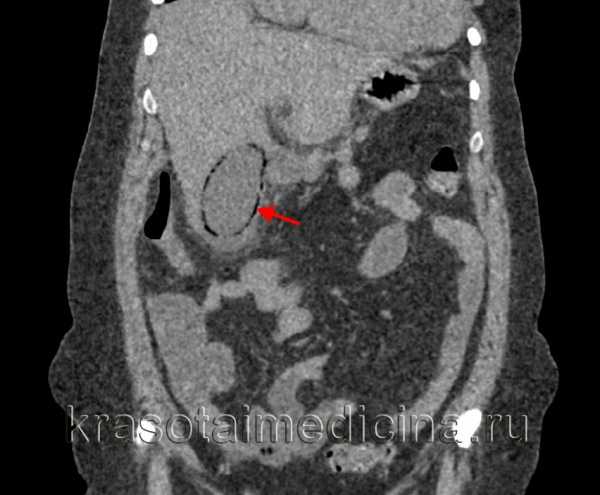

КТ органов брюшной полости. Острый эмфизематозный холецистит – скопление газа по периферии в виде «ободка».